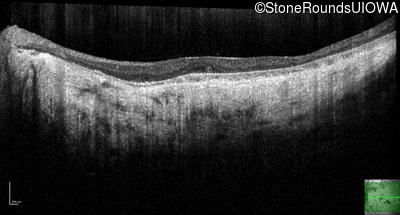

Optical Coherence Tomography - Right - 20/200 -3

Exemplar / OCT Stack

OCT Stack